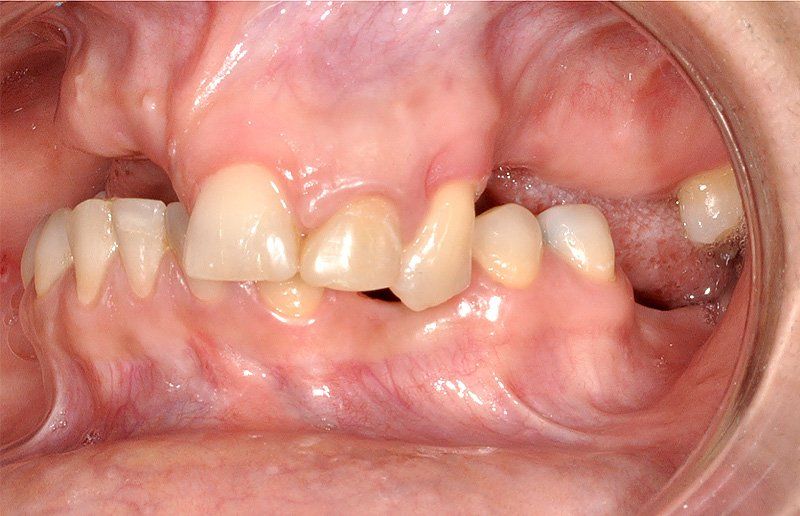

Los Implantes de Carga Inmediata son una solución práctica y definitiva para el desdentado total, es un tratamiento el cual una vez que se opera y se colocan los implantes, por un periodo entre 24 horas a 48 horas, se colocan los dientes en forma provisional, de esta forma el paciente queda con algo fijo mientras el implante se adhiere al hueso. Su principal ventaja radica en la reducción o eliminación del tiempo de espera entre la colocación del implante dental y la colocación de los dientes fijos.

Son recomendables para personas que no están dispuestas a una prótesis removible y quienes quieren acortar los tiempos de espera.